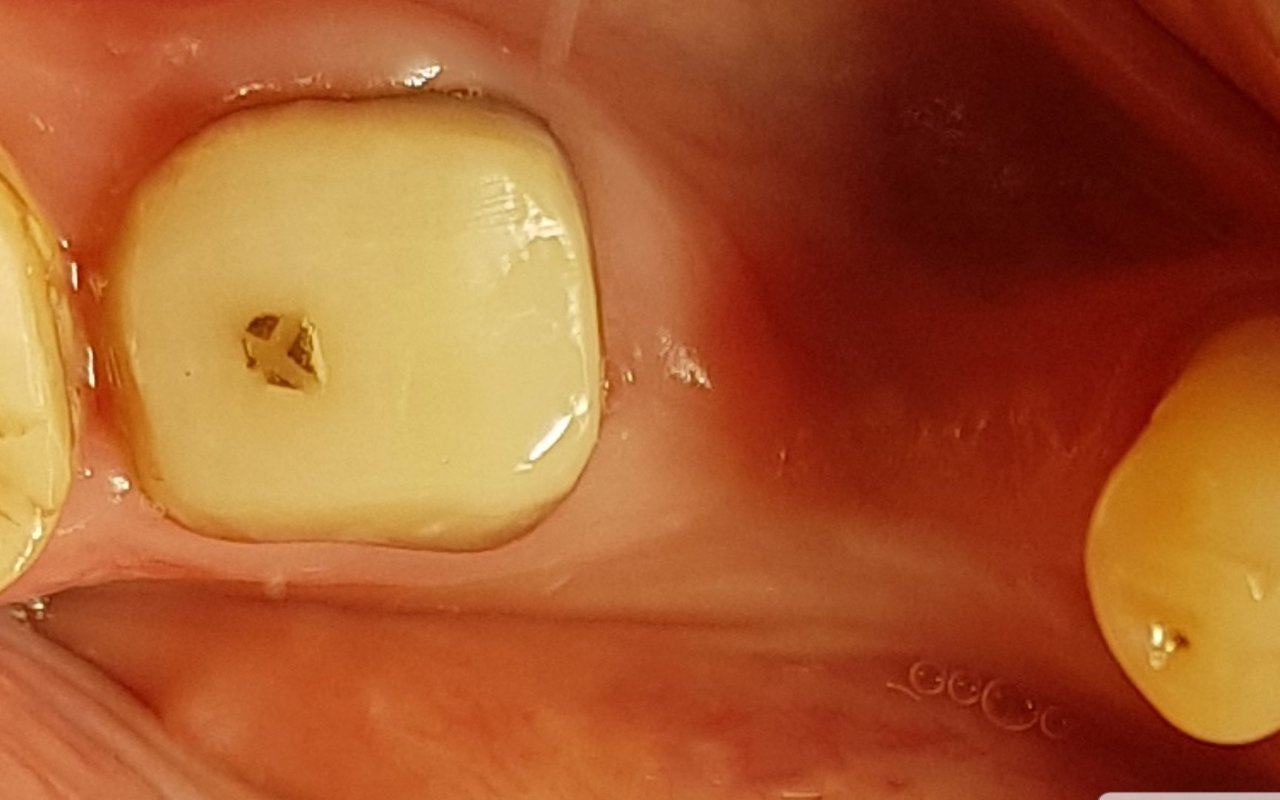

Фото работ врача Андрея Евгеньевича Биктимирова